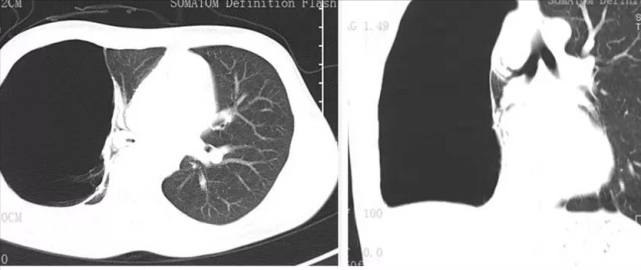

前段时间,王大姐感冒后胸闷的厉害,稍微一活动便气喘吁吁,体温37.7℃,因为疫情药店买不到退热药,没有办法王大姐才去了医院,然而,不查不知道一查吓一跳,胸部CT显示王大姐的胸腔里有个“大气球”,这个气球将右肺压没了,这也正是王大姐多年以来胸闷的“真凶”。

王大姐胸腔里的气球其实叫肺大疱,肺大疱是肺泡的非正常状态。正常的肺泡是肺的组成结构,当内部压力增大时,正常的肺泡壁被压迫乃至破裂,他们彼此融合,在肺组织中形成直径大于1cm的含气囊腔。

王大姐这个肺大疱与普通的肺大疱又有些许不同,因为肺大疱巨大,甚至直径超过10cm, 将其称为巨大肺大疱,它就如同气球一般,长期藏在王大姐的胸腔里。